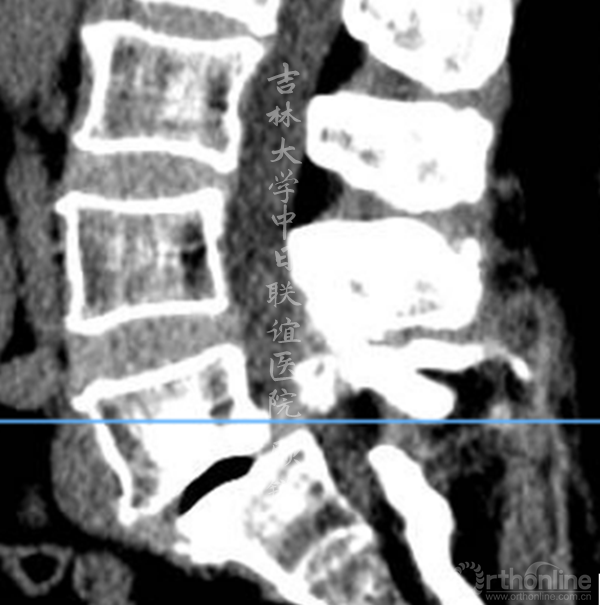

腰椎CT:

(L5-S1)

诊断为:L5峡部裂型滑脱(真性滑脱)(Ⅱ度),腰椎MRI平扫发现异常信号。

滑脱椎体后方椎管内见异常信号,是游离髓核(硬膜内)?椎管内肿瘤(神经源性、转移)?血管畸形?还是其他其他?组内会诊认为以疾病一元论解释患者的症状、体征考虑因滑脱椎导致马尾神经冗余的可能性大。进一步检查了增强腰椎MRI。